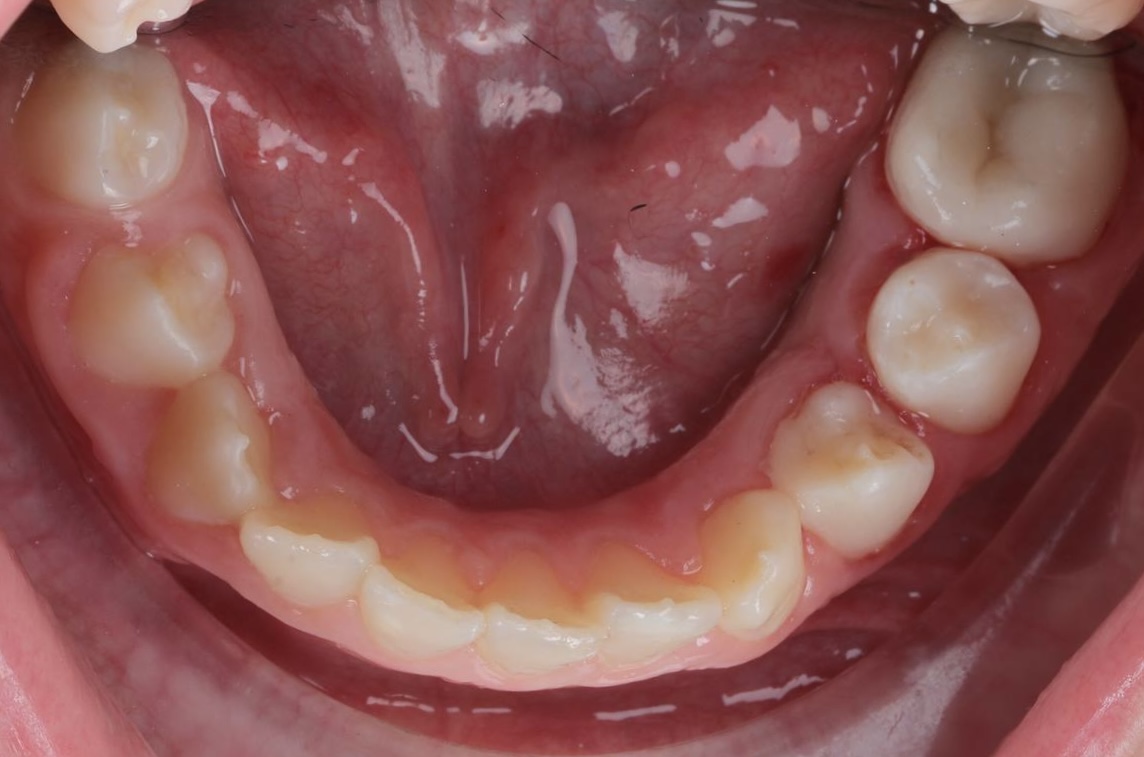

Дитина звернулася до нашої клініки разом із батьками зі скаргами на неправильний прикус. Під час первинного огляду було встановлено, що для досягнення правильного змикання зубів необхідно розпочати лікування з підготовчого етапу.

На представленому фото — результат після першого етапу лікування, на якому вже помітні позитивні зміни прикусу.

Як проходив перший етап лікування

На першому етапі було виконано розширення верхньої щелепи. Для цього дитині встановили незнімний розширювальний апарат на верхню щелепу, який дозволяє:

• створити достатній простір для правильного розташування зубів;

• покращити співвідношення щелеп;

• підготувати зубощелепну систему до наступних етапів ортодонтичного лікування.

Вже після завершення цього етапу прикус почав змінюватися, що є важливим показником ефективності лікування.

Поточний стан і подальший план

На даний момент дитина носить лицьову маску, яка допомагає скоригувати ріст щелеп і закріпити отриманий результат. Після завершення цього етапу планується подальше лікування з використанням брекет-системи для точного вирівнювання зубів і стабілізації прикусу.

Ортодонтичне лікування у дітей часто проходить поетапно, і саме ранній початок дозволяє досягти більш прогнозованого та стабільного результату в майбутньому.